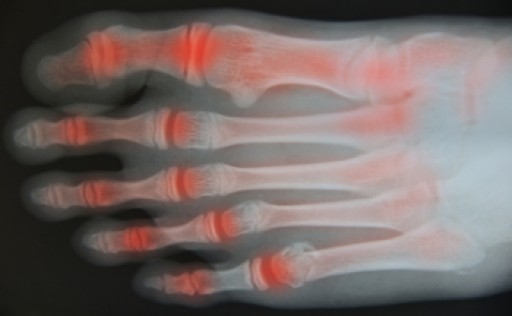

Osteoarthritis is a common joint disease that is caused by degeneration of cartilage, a layer of tissue that lines the ends of bones and helps them move smoothly. When the cartilage is worn away, the bones begin to rub directly against each other as they move, leading to pain, swelling, and joint stiffness. Osteoarthritis often affects the joints in the feet and ankles. In addition to the symptoms of arthritis itself, this condition can also cause other foot problems, such as bunions, hallux rigidus, and corns and calluses. Osteoarthritis is associated with aging and tends to affect people over age 45. People who are overweight or obese, have a family history of osteoarthritis, or have a medical history of rheumatoid arthritis or gout are most at risk. If you are experiencing symptoms of osteoarthritis in your feet or ankles, please consult with a podiatrist.

Arthritis is a term that is commonly used to describe joint pain. The condition itself can occur to anyone of any age, race, or gender, and there are over 100 types of it. Nevertheless, arthritis is more commonly found in women compared to men, and it is also more prevalent in those who are overweight. The causes of arthritis vary depending on which type of arthritis you have. Osteoarthritis for example, is often caused by injury, while rheumatoid arthritis is caused by a misdirected immune system.

Arthritic symptoms range in severity, and they may come and go. Some symptoms stay the same for several years but could potentially get worse with time. Severe cases of arthritis can prevent its sufferers from performing daily activities and make walking difficult.